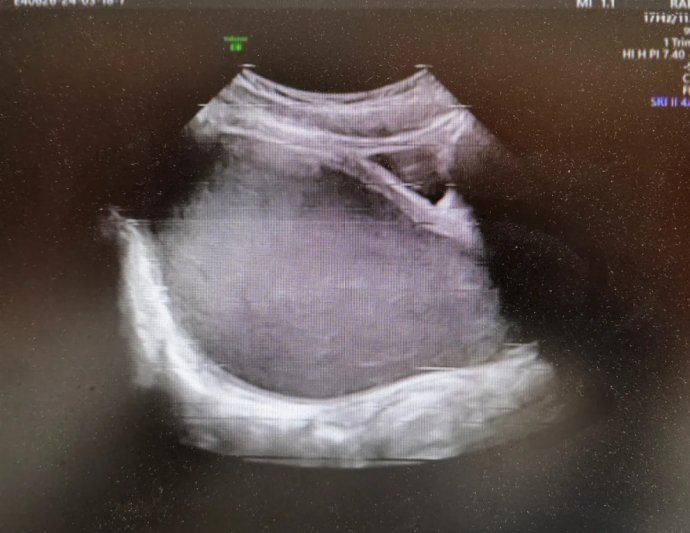

12歲花季少女出現周期性下腹痛,在其父母帶領下先后就診咸陽市兩家醫院,最終,她們選擇了延安大學咸陽醫院婦科。就診當日,趙倩蘭主管醫生詳細追問病史,患者自訴已間斷性下腹痛3月余,本次腹痛較前明顯加重,腹痛難忍。入院后醫生立即為其安排了婦科彩超及盆腔磁共振,發現該患者宮腔、宮頸及陰道上段充滿大量積血,積液壓迫膀胱及直腸,導致排便、排尿障礙。張素寧主任為其查體后發現,該患兒陰道竟無開口,導致經血無法排出,閉鎖處無隆起,無青紫,排除處女膜閉鎖,直腸檢查發現陰道上端有一包塊凸向直腸,包塊下緣距離肛門口約4-5cm,結合查體及相關輔助檢查,考慮該患者為陰道閉鎖,值得慶幸的是該患者其他系統暫未發現畸形。

婦科超聲圖